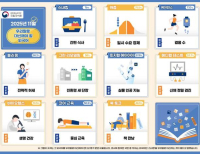

이번 혁신제품에는 건강·의료(9개), 생활안전·재해예방(8개), 교통·환경개선(12개), 에너지 절감(4개) 등 국민건강 증진, 사회안전예방과 같은 공공서비스 향상에 기여할 수 있는 다양한 분야의 우수제품들이 지정됐다.

주요 제품으로는 건강·의료분야의 폐암 조기진단을 위한 ‘CT영상 판독시스템’과 복부 대사질환의 위험도를 예측하는 ‘AI 기반 대사질환 분석 시스템’ 등이 있으며, 안전·재해예방 분야는 ‘다목적 휴대용 방사선 오염측정기’와 ‘감염성 폐기물 밀봉포장 처리기’, 가스누출을 자동감지해 화재·폭발사고를 예방해주는 ‘다기능 loT 가스콕’ 등이 있다.